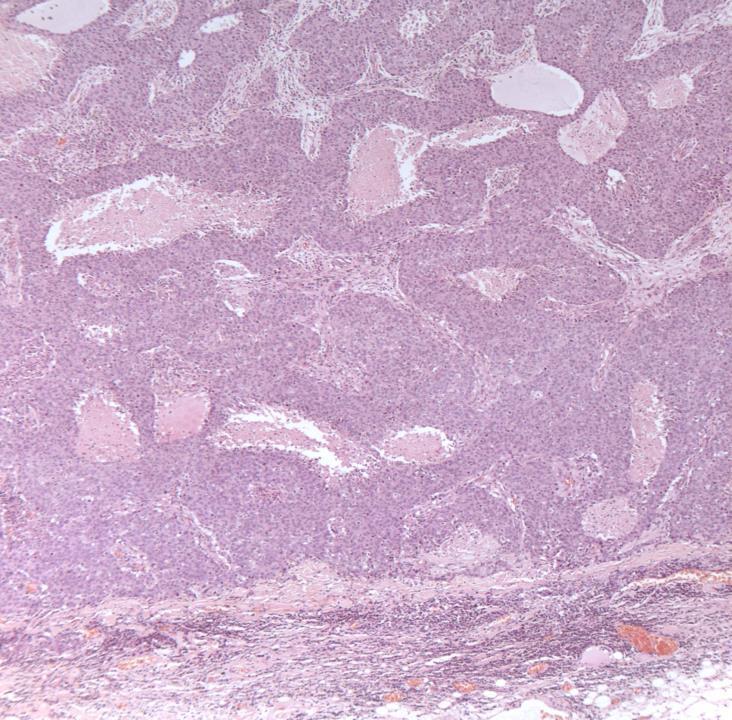

Case 19

◼ Fibroepithelial lesion

◼ Stromal overgrowth

◼ Stromal cellularity

◼ Leaf-like pattern

◼ Stromal atypia

◼ Infiltrative margin

◼ Phyllodes tumour (borderline)

◼ Cellular fibroepithelial lesion and benign phyllodes are managed similarly.

◼ Borderline and malignant phyllodes: excision with margin.